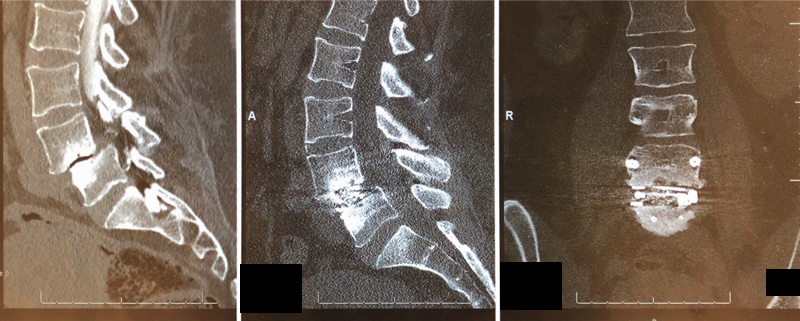

SPONDYLOLISTHESIS

Spondylolisthesis is a condition in which a vertebra slips out of alignment with the rest of the spinal cord, leading to spinal instability. The slipped vertebra may put pressure on the disc or bone below it, but the condition does not always lead to symptoms and it is possible to live unaware of it for years. In some cases the slipped vertebra may compress a nerve, resulting in pain and other symptoms. See radiculopathy for more details. Spondylolisthesis is usually caused by trauma due to injury, age-related degeneration, or a malformation in the spine either before birth or during adolescence.

Spondylolisthesis can often be treated with pain medication and physical therapy to strengthen the abdominal and back muscles. If your pain is chronic and severe, or if it persists after trying conservative treatments, Dr. Li may recommend spinal fusion surgery.